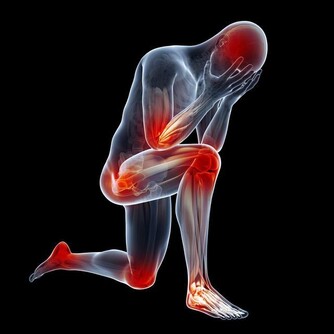

絕經後由於雌激素突然和明顯的缺乏會引起一些不適,有人在絕經前期就可發生。常表現為心情和情緒的變化,煩躁、易激動、失眠,焦慮,陣發性臉潮紅、潮熱、出汗,皮膚瘙癢、有時皮膚還有蟻爬的感覺,並且皮膚失去彈性,皺紋增多,肌肉逐漸鬆弛,時有疼痛,易疲勞或乏力、頭疼、頭暈和血壓不穩等。

這些症狀叫做更年期綜合徵。